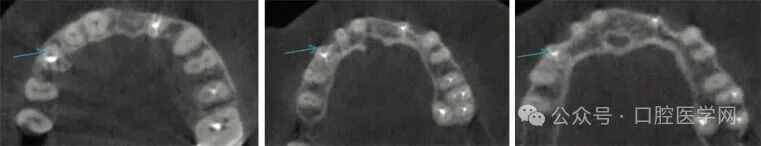

常规根尖片显示右上尖牙根管充填不完全,根尖区有大范围的透射影,牙周韧带间隙消失,硬骨板增宽,如图3所示。但常规片无法明确充填材料是位于根管内还是根管外,也不能准确判断哪颗牙齿是症状的真正来源。CBCT检查证实牙周韧带间隙内存在与根管相邻的不透射充填材料,而根管本身呈空虚状态,如图4和图5所示。尖牙根尖以外未发现被挤压出的充填材料。

图5 横断位锥形束计算机断层扫描显示13号牙牙周韧带间隙内根管充填不充分,根尖区有大面积透射影。